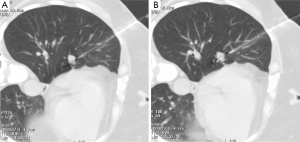

A 52-year-old lifetime non-smoker female with no significant past medical and surgical history presented for a routine follow-up of a right lower lobe solitary pulmonary nodule. This nodule was incidentally detected on a CTA chest performed in 2012 to rule out a pulmonary embolus (Figure 1). After the initial scan in 2012, the patient was lost to follow-up for two years and presented again in 2014. CT scan of the chest now showed that the right lower lobe non-calcified pulmonary nodule had grown in size (Figure 1B). A one year follow-up with a CT scan of the chest showed that the lung nodule had doubled in size over three years, highly suspicious for malignancy (Figure 1C). PET/CT showed mild uptake in the enlarging pulmonary nodule (Figure 1D). Subsequently, a CT-guided biopsy of the nodule revealed a carcinoid tumor (Figure 2). Next, the patient underwent a right middle lobectomy with an uncomplicated recovery (Figure 3A). Pathology results showed a well-differentiated NET with more than 2 mitoses per 10 hpf with no atypia or necrotic foci (Figure 3B,C), consistent with an atypical lung carcinoid. Tumor cells stained positive for cytokeratin 7, TTF-1, chromogranin A (CgA), synaptophysin, and negative for CK20, with Ki-67 proliferation index of 1% (Figure 3D), consistent with a lung carcinoid. Follow-up imaging showed no local spread or distant metastases. The patient is disease free till date, consistent with cure.